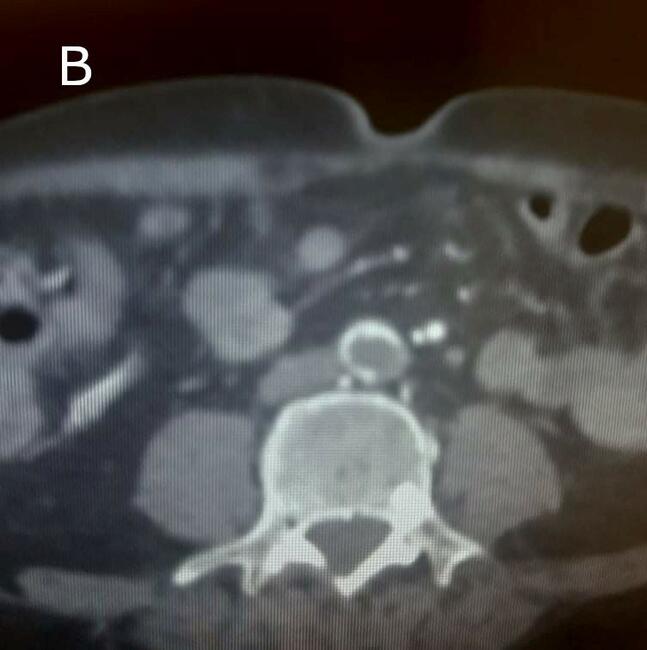

Anatomic location of thrombosis was found on the lower limb in 21 patients (84%) and 4 (16%) presented with upper limb ischemia, with femoral (48%) and brachial (8%) arteries being the most affected. Aortic thrombus was revealed in 7 cases (Figure 1).

All patients required urgent operative intervention. Thrombectomy was performed in 24 patients (96%) and only 1 patient had peripheral vascular bypass. A retrograde transfemoral and popliteal thrombectomy were performed, respectively, in 15 and 6 patients with acute lower limb ischemia. Distal arteries were approached selectively in only 1 patient. Brachial and radial thrombectomy were performed in 4 patients. None of the patients needed fasciotomy. Limb salvage was obtained for all patients except one. Surgical features and anatomic location of the occlusion are summarized in Table 2. Histological examination showed a widely ulcerated endothelial lining with formation of an obliterating thrombosis (Figure 2).